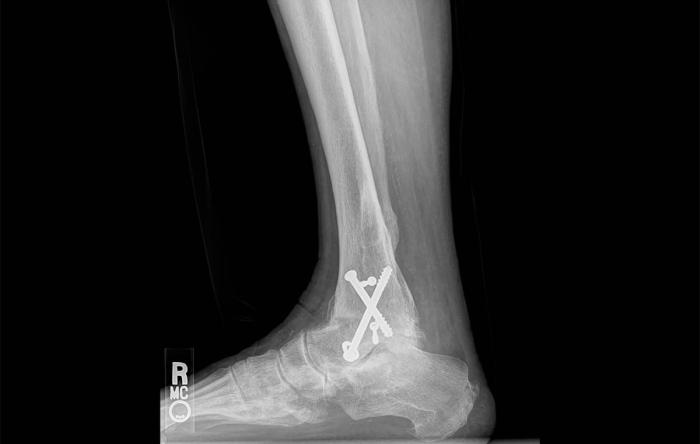

The surgery involves removing damaged cartilage and precisely aligning the bones of the ankle. Surgeons then use metal plates, screws, or rods to hold the bones together until they naturally fuse. This process reduces pain and inflammation, and allows patients to regain balance and function over time.